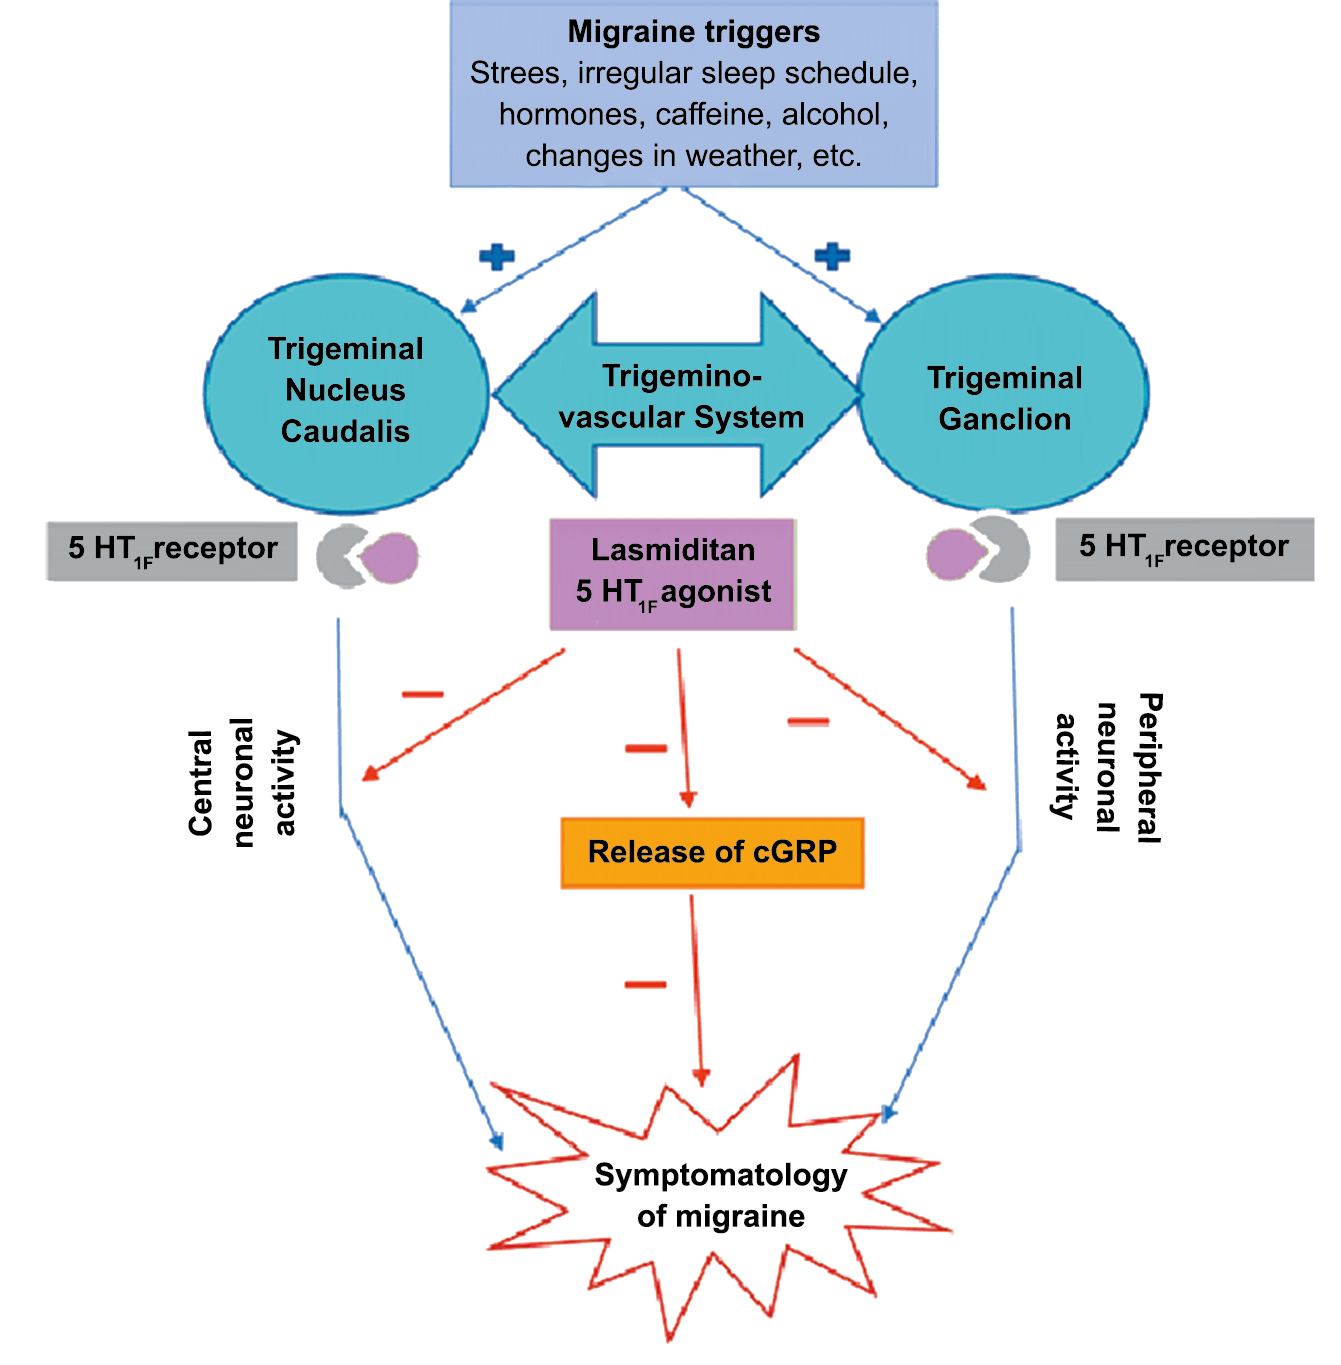

El CGRP es un potente vasodilatador que, cuando se administra a personas que padecen migrañas, se sabe que desencadena ataques(72). Se libera durante los ataques espontáneos(73) o provocados(74), que pueden inhibirse mediante el tratamiento con triptanos(75). Además de sus efectos vasculares, CGRP se ha convertido en un modulador clave de la función neuronal, que tiene efectos importantes en los sistemas de neurotransmisores como el sistema glutamatérgico(76). Sobre la base de los datos clínicos(77), se inició un esfuerzo para desarrollar antagonistas de los receptores de CGRP: los “gepantes”: telgacepant demostró una eficacia mejor que el placebo y comparable a los triptanos(78), como el primer antagonista oral del receptor de CGRP con excelente tolerabilidad a largo plazo(79) y también fue bien tolerado en pacientes que estaban siendo investigados por enfermedad arterial coronaria(80). Sin embargo, el desarrollo de telgacepant se detuvo cuando surgieron problemas con las enzimas hepáticas en un estudio preventivo, que resultó bastante positivo(81). Este efecto no se ha informado con rimagepant(82) Los ditanes, tienen como mecanismo el ser agonistas selectivos del receptor 5-hidroxitriptamina tipo 1F (5-HT1F) en la vía trigeminal, hasta ahora ha demostrado no tener efecto vasoconstrictor asociado. Lasmiditán ha sido hasta la fecha de elaboración de esta revisión la primera molécula aprobada por FDA. (Figura 35)

La comprensión de la biología de la migraña a través de una cuidadosa investigación de laboratorio ha llevado al desarrollo de las principales clases de tratamientos: triptanos, agonistas del receptor de serotonina 5-HT1B/1D; gepants, antagonistas del receptor del péptido relacionado con el gen de la calcitonina (CGRP); ditanes, agonistas del receptor 5-HT1F, CGRP anticuerpos monoclonales; moduladores de mGlu5, sin olvidar el efecto ya demostrado por parte de los bloqueantes de los canales de calcio (flunarizina) y de los neuromoduladores; bien se trate de topiramato (Inhibe la acción de la anhidrasa carbónica, bloquea los canales del sodio, aumenta las corrientes de cloro mediadas por GABA, activa las corrientes hiperpolarizantes del K+ e inhibe la activación de receptores a ácido glutámico tipo AMPA), valproato de sodio (Inhibe las enzimas de degradación del GABA y puede aumentar su síntesis, además de tener un papel inhibidor de la transmisión excitatoria de ciertos aminoácidos, entre ellos el glutámico y reducir el umbral de conductancia del calcio y el potasio) y de los antidepresivos de diversas clases como la amitriptilina (antidepresivo tricíclico que impide la recaptación y la inactivación de la noradrenalina y la serotonina en las terminaciones nerviosas) y venlafaxina (inhibe principalmente la recaptación de serotonina y en menor grado de noradrenalina, en la membrana presináptica neuronal, potenciando la neurotransmisión a nivel del sistema nervioso central). El propanolol tiene un efecto antagonista de los adrenoceptores β1 en las neuronas del núcleo VPM (postero medial ventral) del tálamo que responden a la entrada nociceptiva trigeminovascular. Se ha demostrado que el propanolol previene los cambios en el comportamiento y el flujo sanguíneo cerebral inducido por la depresión cortical propagada, además de bloquear los canales de sodio del cerebro(103), modulación del sistema catecolaminérgico central(104) probablemente a través de receptores β-adrenérgicos centrales e interacción cruzada con receptores de serotonina(105) (Figura 4).